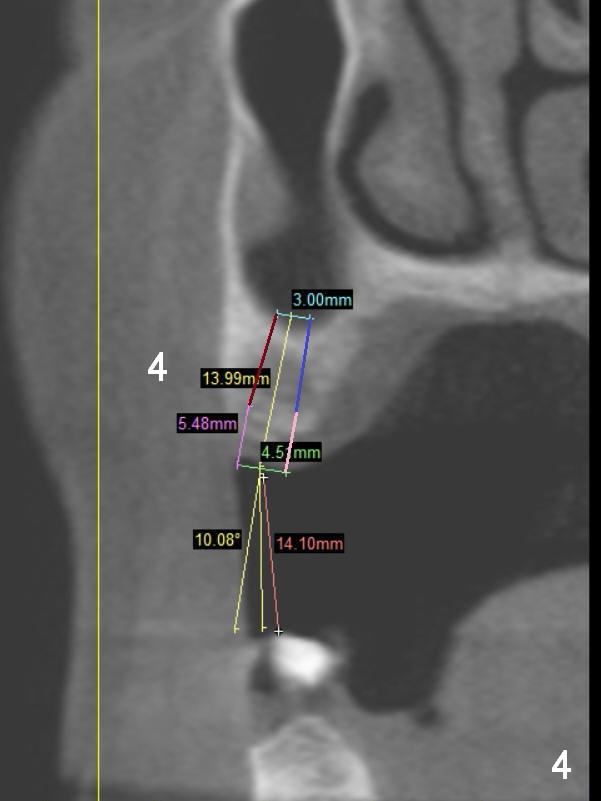

A 68-year-old lady has several missing teeth (Fig.1,2).  She has agreed to have an implant at the site of #3 (Fig.3) to stabilize an upper removable partial denture (RPD).  The latter will be more stable if an extra implant is placed at #6 (Fig.1,2,6).  There is enough bone to place implants at #4,5 (Fig.4,5).  Bone density at these sites is low.  Osteotomy should be underprep with bone condensation.  Edentulous space is high so long abutments are required (9 mm instead of 3 or 5 mm (regularly used)).  Angled abutments should be prepared.